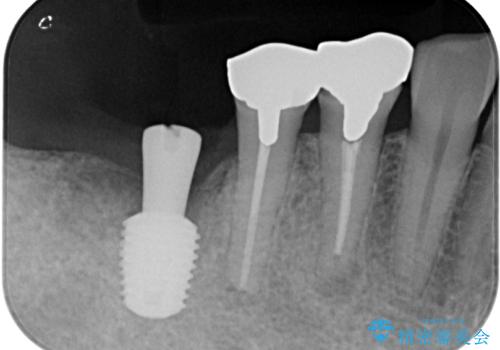

- 「歯を抜いたので、インプラントを入れてほしい」という主訴で来院された患者様です。

他院で歯根破折により抜歯をしたとのことでした。

CTにより残存骨量を確認しインプラント埋入を行っていくこととしました。

今後手前の根管治療を行っている歯が歯根破折を起こして抜歯になる可能性を想定して手前の歯に平行にインプラント埋入を行っています。